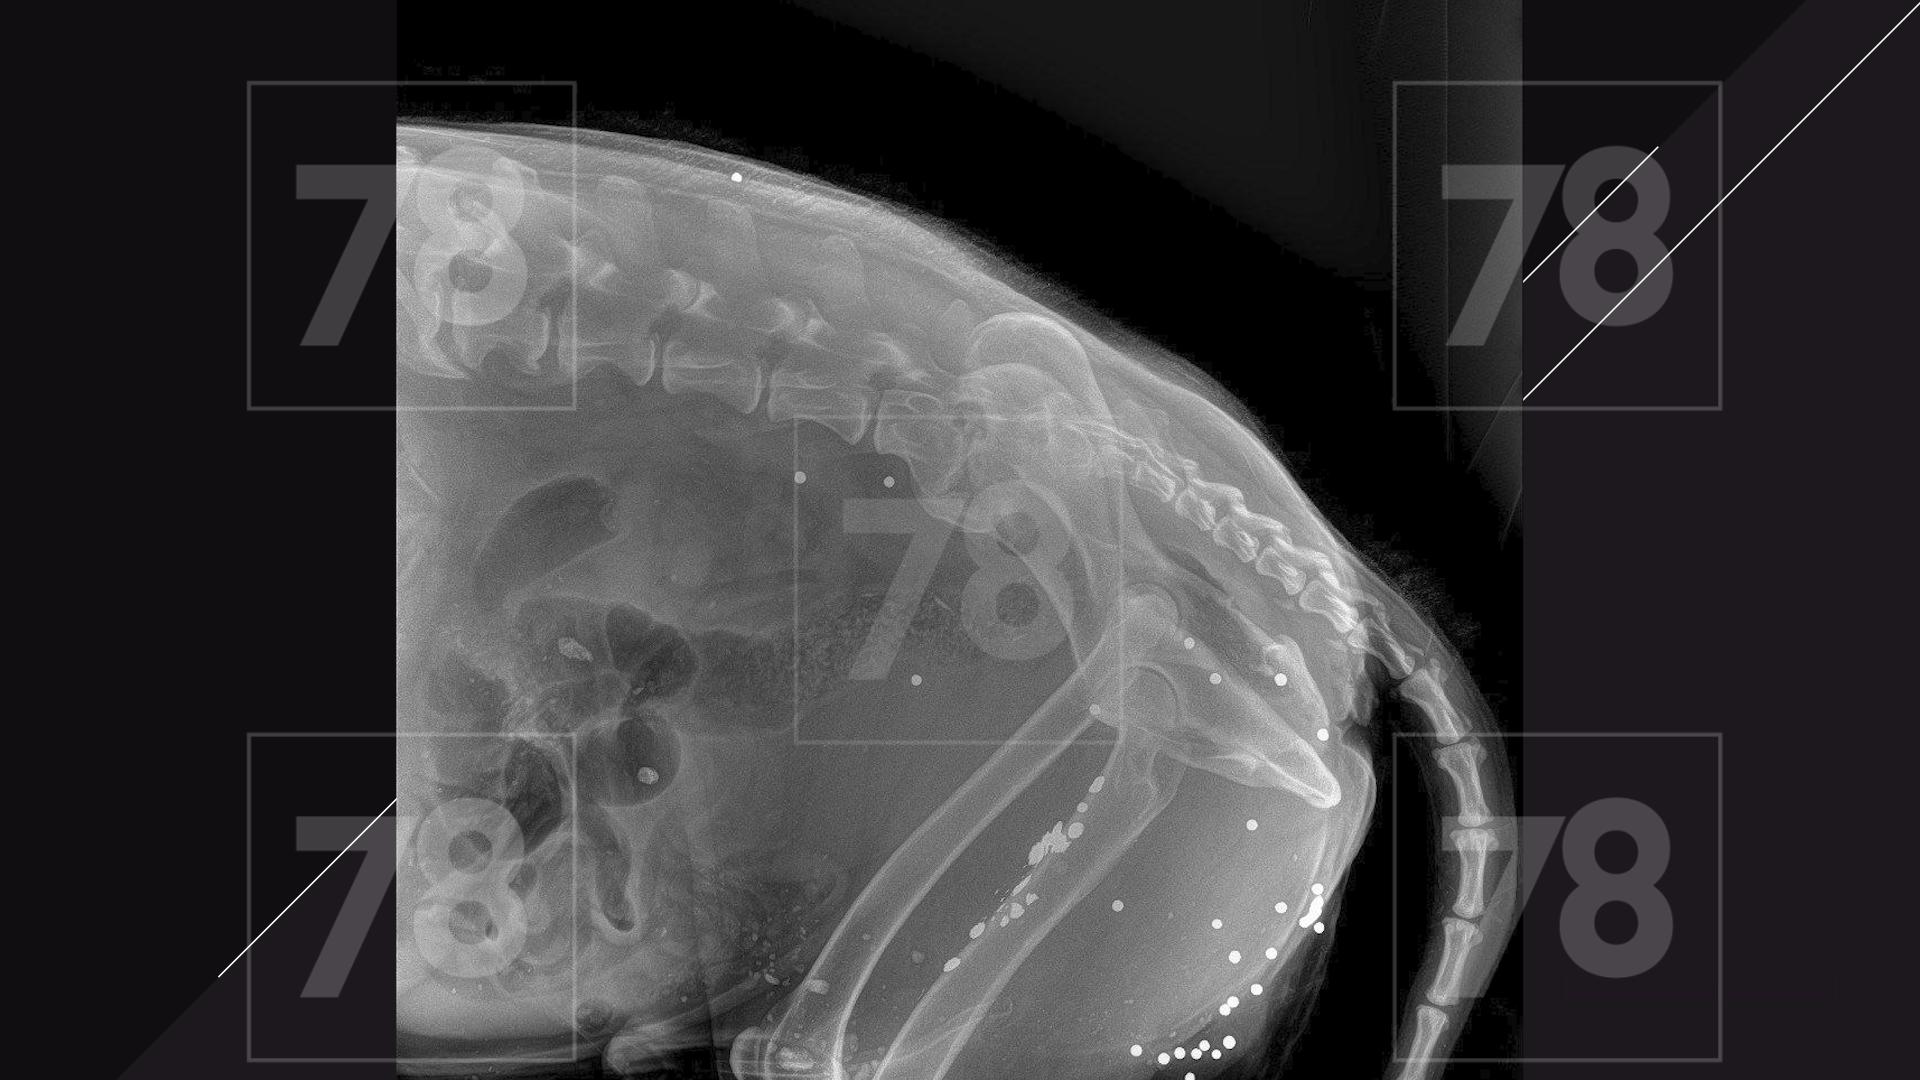

Врачи обнаружили у собаки множественные ранения пулями, как свежие, так и старые.